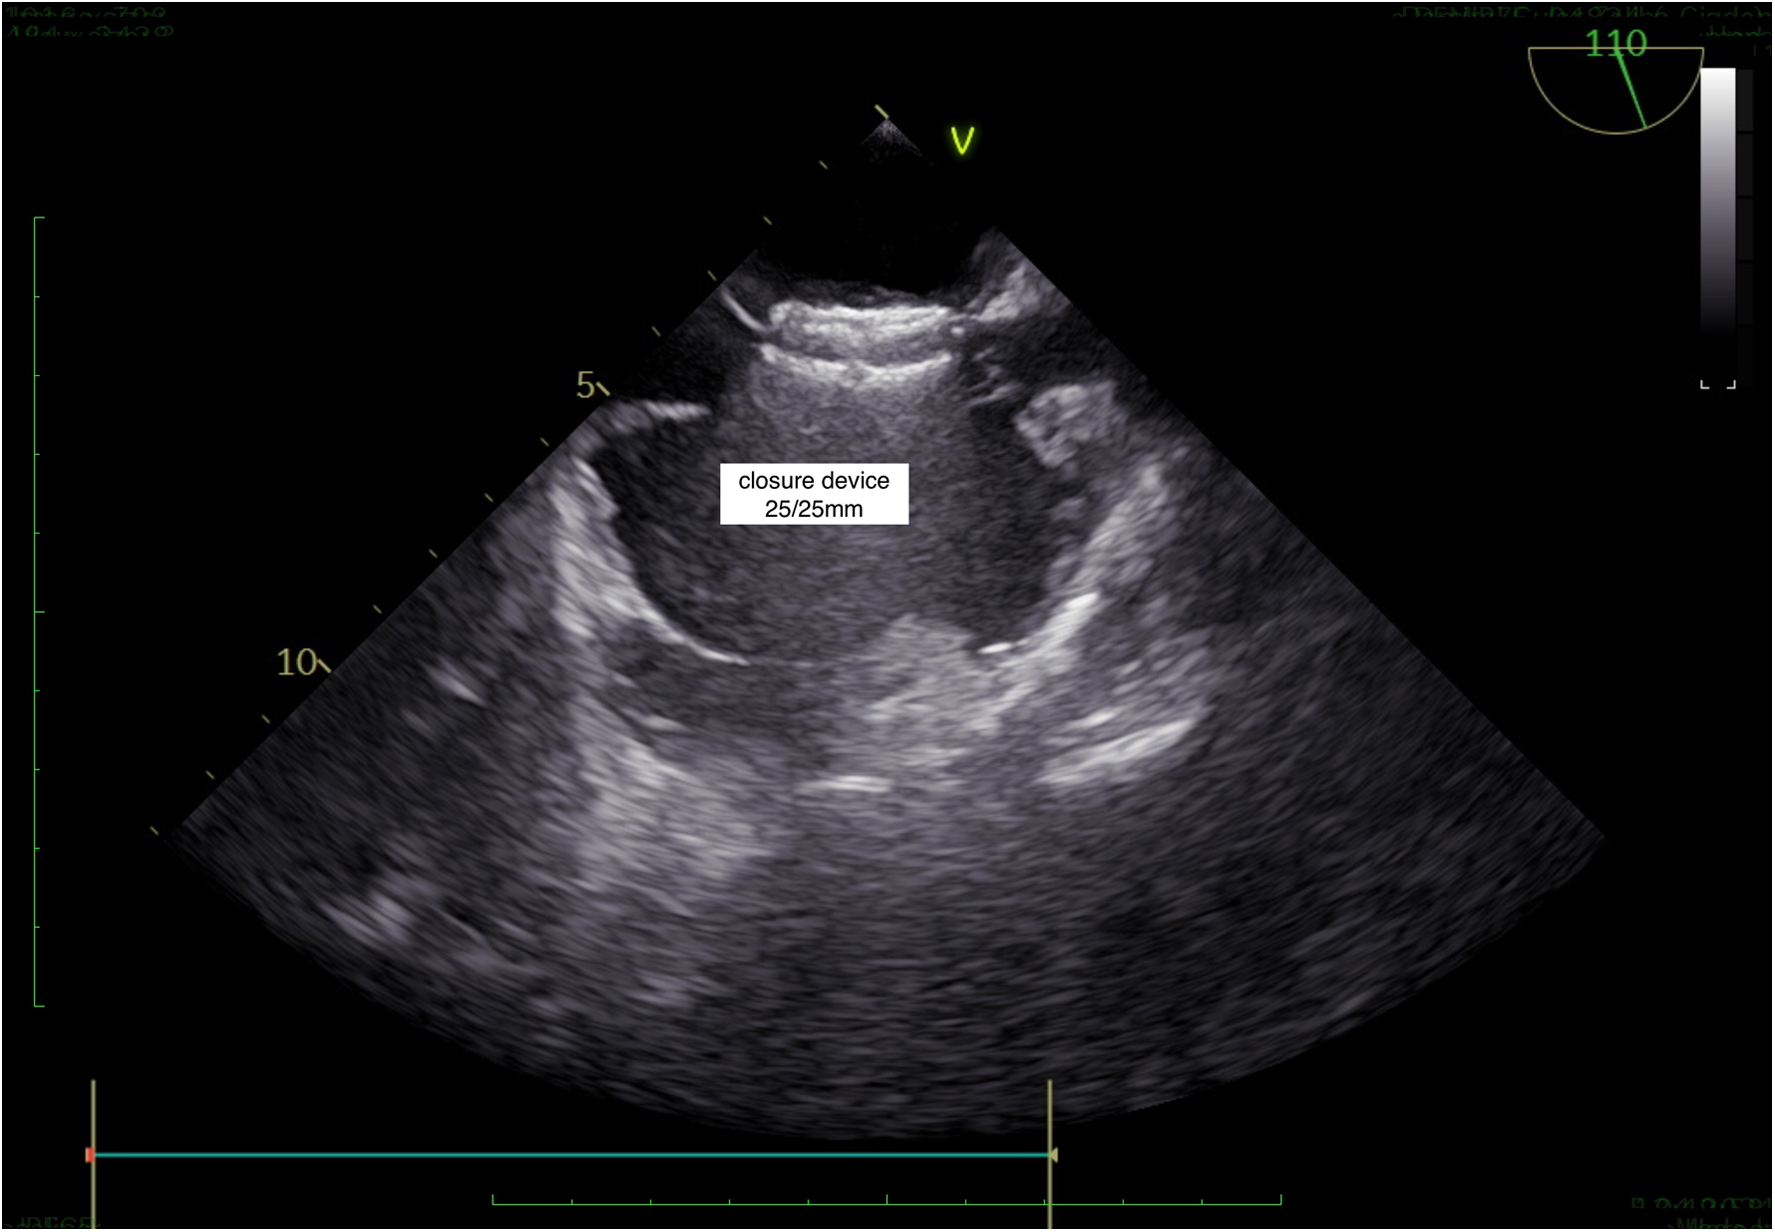

Figure 5

TEE, successful PFO closure.

A long introducer sheath was then inserted over the wire and the device was placed using the standard technique. First, the left side disc was released and the whole system was pulled back till the left atrial disc contacted the septum, and then the right atrial disc was released.

The position and stability of the device were checked using the Minnesota maneuver. Finally, the device was fully released.

The procedural success was very high (100%). However, after the procedure, moderate pericardial effusion developed in one patient (0.7%) and it was treated medically. In addition, in the first month, an acute pulmonary embolism caused by femoral vein thrombosis was observed in one patient, which was resolved with successful medical therapy (0.7%).

The detailed transseptal technique has been routinely used for the closure of PFOs in our cardiology clinic. We use the detailed transseptal technique under the guidance of bicaval and anterior-posterior imaging for tunnel entry and exit in two projections of TEE imaging. In this study, we showed that the detailed transseptal technique for the closure of PFOs was safe and effective when performed by experienced operators. Our study had 144 patients. To our knowledge, this is the largest study to evaluate the closure of PFOs using the transseptal technique. The population encompassed patients with cryptogenic stroke. The success rate of our technique was 100%. It had low postoperative complications, which included perforation and cardiac tamponade (<1%).